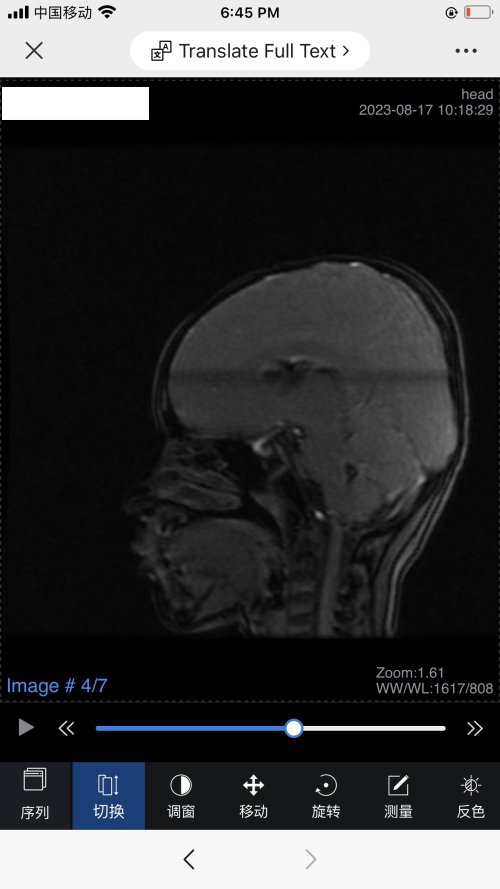

反馈下情况,孩子在国内的医院已经进行过一轮全面检测,没发现什么问题,但是现象是存在的。医生也没什么办法。医生说核磁共振和脑电图没问题,我们也不是很看得懂,各位如果懂的,请指点一下。另外进行了部分基因检测,没发现异常。下一步,我们国庆后打算去更权威的医院去碰碰运气。谢谢各位!

513.6 KB 查看: 103

532.8 KB 查看: 142

551 KB 查看: 132

526.8 KB 查看: 133

510 KB 查看: 103

506.4 KB 查看: 124

495.7 KB 查看: 165